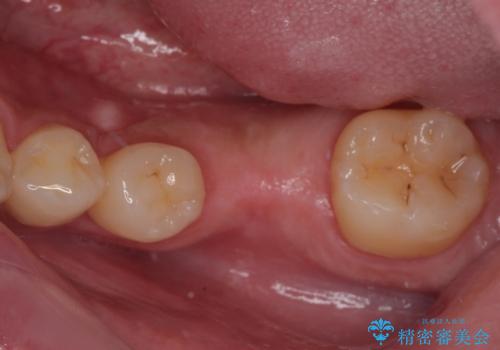

- 左下欠損部のインプラント治療を希望して来院された患者様です。

左下の欠損部を長期間欠損を放置していたことで、咬み合う上の奥歯が動いてしまっている状態でした。